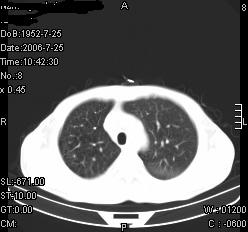

患者,男,54岁,咳嗦,咳痰20天。抗炎治疗2周。现esr76mm/h,目前患者症状明显好转,但发现两次ct片未见明显变化。两次分别做与7.25、7.31。第一次诊断右肺上叶炎症累计胸膜。大家看,从影像上内排除结核吗?

结核的可能性非常大,右上肺病变应该考虑干酪性肺炎。理由:

1.纵隔内多发淋巴结肿大。

2.esr76mm/h。

3.虽经抗炎治疗肺窗病灶有所吸收、减小,但纵隔窗病灶形态、密度、范围无明显变化。如果是单纯的大叶性肺炎,“抗炎治疗2周,目前患者症状明显好转”病灶应该基本消散了,至少也处于吸收消散期,密度变淡、范围变小。同时本病例所示其内的密度不均匀,见多发大小不一空洞样影也不符合大叶性肺炎吸收消散期表现。

病灶特点:片状 索条 结节混杂影,部分融合,密度不均,广泛累及相应胸膜.

临床治疗;二周未吸收.但症状好转.

多考虑:肺结核.